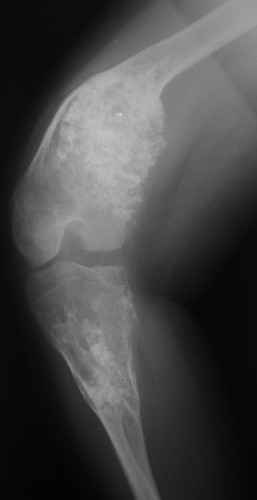

Деформация правой нижней конечности с 6 месяцев (стала прогрессировать после года, с момента начала ходьбы). Поставлен диагноз болезнь Олье, варусная деформация, укорочение правой нижней конечности на 4,5 см. 1993 г. - операция остеоклазия на уровне очагов поражения в н/3 правой бедренной кости и в/3 правой большеберцовой кости с одномоментной коррекцией деформации и фиксацией костных фрагментов спицами Киршнера.После начала статической нагрузки (1994 г.) появился рецидив деформации и укорочения. Вторая операция - ЧКО АВФ, аппарат демонтирован через 2недели в связи с развившимся на уровне стержня переломом, после чего находилась в гипсовой повязке до консолидации костных фрагментов. Далеелечилась консервативно в гипсовой повязке. Выраженная деформация и укорочение правой нижней конечности. Относительная длина бедер: справа -34 см, слева - 51 см; анатомическая длина голеней: справа - 29 см, слева - 39 см. Величина варусной деформации на уровне дистального отдела правого бедра составляет - 80 град. Амплитуда движений в коленных суставах (разгибание/сгибание ): справа - 0/0/100 град.; слева - 0/0/30 град. Отмечается боковая и ротационная нестабильность на уровне правого коленного сустава. Амплитуда движений в голеностопных суставах - в норме. Тактика лечения? Заранее благодарю! С уважением,А.В.Владзимирский

Высылаю вам фото подобной больной, у нее тоже первая попытка до меня была безуспешной.

Нужен аппарат Илизарова стабильный с множеством спиц с напайкой, временной фиксацией колена аппаратом на голени. Наверное, проще первый раз начать с бедра, остеотомию выполнить прямо на уровне перехода очага в дистальный метафиз бедра. Дистракционный остеогенез вызовет перестройку хрящевой ткани в костную. Понадобится еще пара этапов.